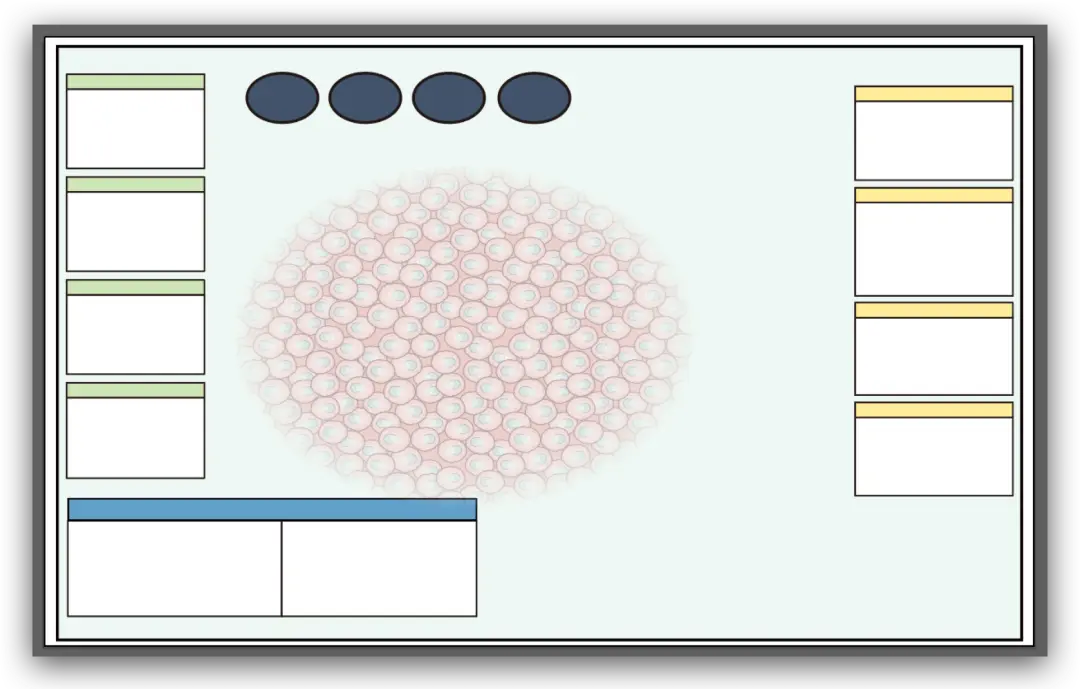

来,实现下面的图

整体构架完成了

接着上面,我们先把画框底色改为浅蓝色

然后来画最中间这部分粉色细胞

排版一下

完成了

排版上去

排版一下

完成了